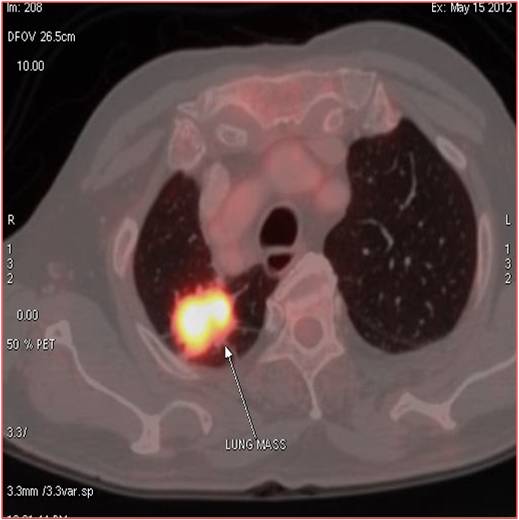

CT scan of the abdomen confirmed the findings ; For further clarification PET whole body scan was done at a centre in Chennai. The following images are from that.

Heterogeneously enhancing irregular spiculated soft tissue mass measuring ~ 34 x 29 mm noted in the apical segment of right upper lobe. The lesion abuts the pleura posteriorly.

FDG avid enhancing lymph nodes noted in right and left paratracheal regions, largest measuring ~ 19 x 11 mm on the right side.

- Metabolically active spiculated right upper lobe lung mass – likely malignant primary.

Mediastinal and retroperitoneal FDG avid metastatic lymphadenopathy.